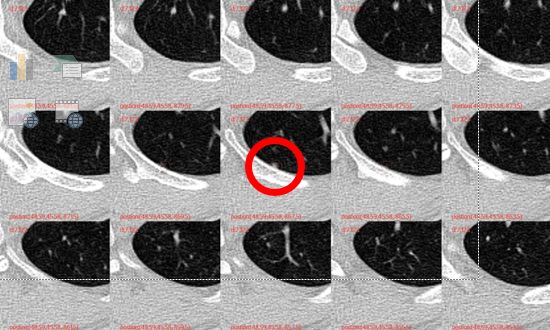

此外,在疑难位置,也依然存在部分AI检出而医生未检出,医生检出而AI未检出的情况,需要以“AI+医生”的形式进行互补。

血管旁结节(图片来源:医学影像服务中心)